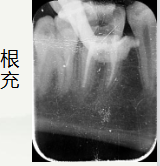

右下第一磨牙颌面大面积坏,可探及腔,叩+,无松动,无冷热刺激敏感。辅助检查:X线片显示左下第一磨牙远中邻面阴影,颌面阴影近腔,根尖口闭合,根尖无明显暗影。右下第一磨牙颌面大面积缺损,顶呈半散开状,根尖区闭合,伴根尖暗影。诊断:左下第一磨牙:急性牙髓炎

通过术前照与X线片,小牙片可见,颌面龋坏,远中邻面龋坏,叩+,松动-,

夜间自发痛,冷热刺激与对照牙对比反应明显。诊断为急性牙髓炎